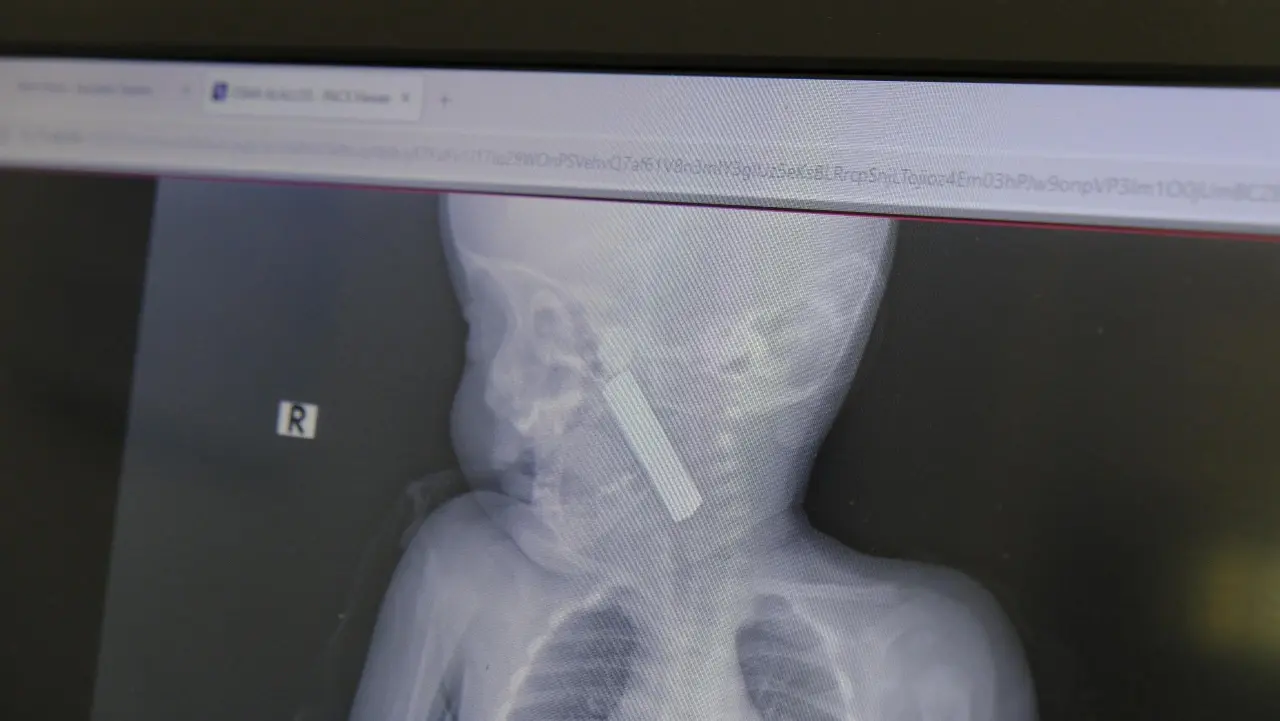

Edinilen bilgiye göre, kusma şikâyetiyle ailesi tarafından Karaman Eğitim ve Araştırma Hastanesi Acil Servisi’ne getirilen 6 aylık E.A. isimli kız bebeğin yapılan muayene ve tetkiklerinde boğazına kumanda pili kaçtığı tespit edildi. Solunum sıkıntısı da yaşayan bebek, vakit kaybetmeden ameliyata alındı.

Çocuk Cerrahisi Uzmanı Doç. Dr. Mehmet Uysal tarafından gerçekleştirilen operasyonla, bebeğin boğazına kaçan pil başarıyla çıkarıldı. Müdahalenin ardından bebeğin solunum problemleri bir süre devam ettiği için 24 saat gözetim altında tutulduğu öğrenildi. Yapılan kontrollerde herhangi bir olumsuzluk tespit edilmemesi üzerine bebek, kontrole gelmek üzere taburcu edildi.

Olayla ilgili açıklama yapan Doç. Dr. Mehmet Uysal, bebeğin hastaneye getirildiğinde ciddi solunum sıkıntısı yaşadığını belirterek, “Yaptığımız tetkiklerde ağız tabanına oturmuş ve yemek borusunun ilk darlığına kadar uzanan kumanda pili tespit ettik. Hastamız siyanotik durumdaydı ve oksijen satürasyonu düşüktü. Bu nedenle beklemeden ameliyathaneye aldık ve yabancı cismi hızlı şekilde çıkardık. Erken müdahale edilmesi olası ağır sonuçların önüne geçti” dedi.